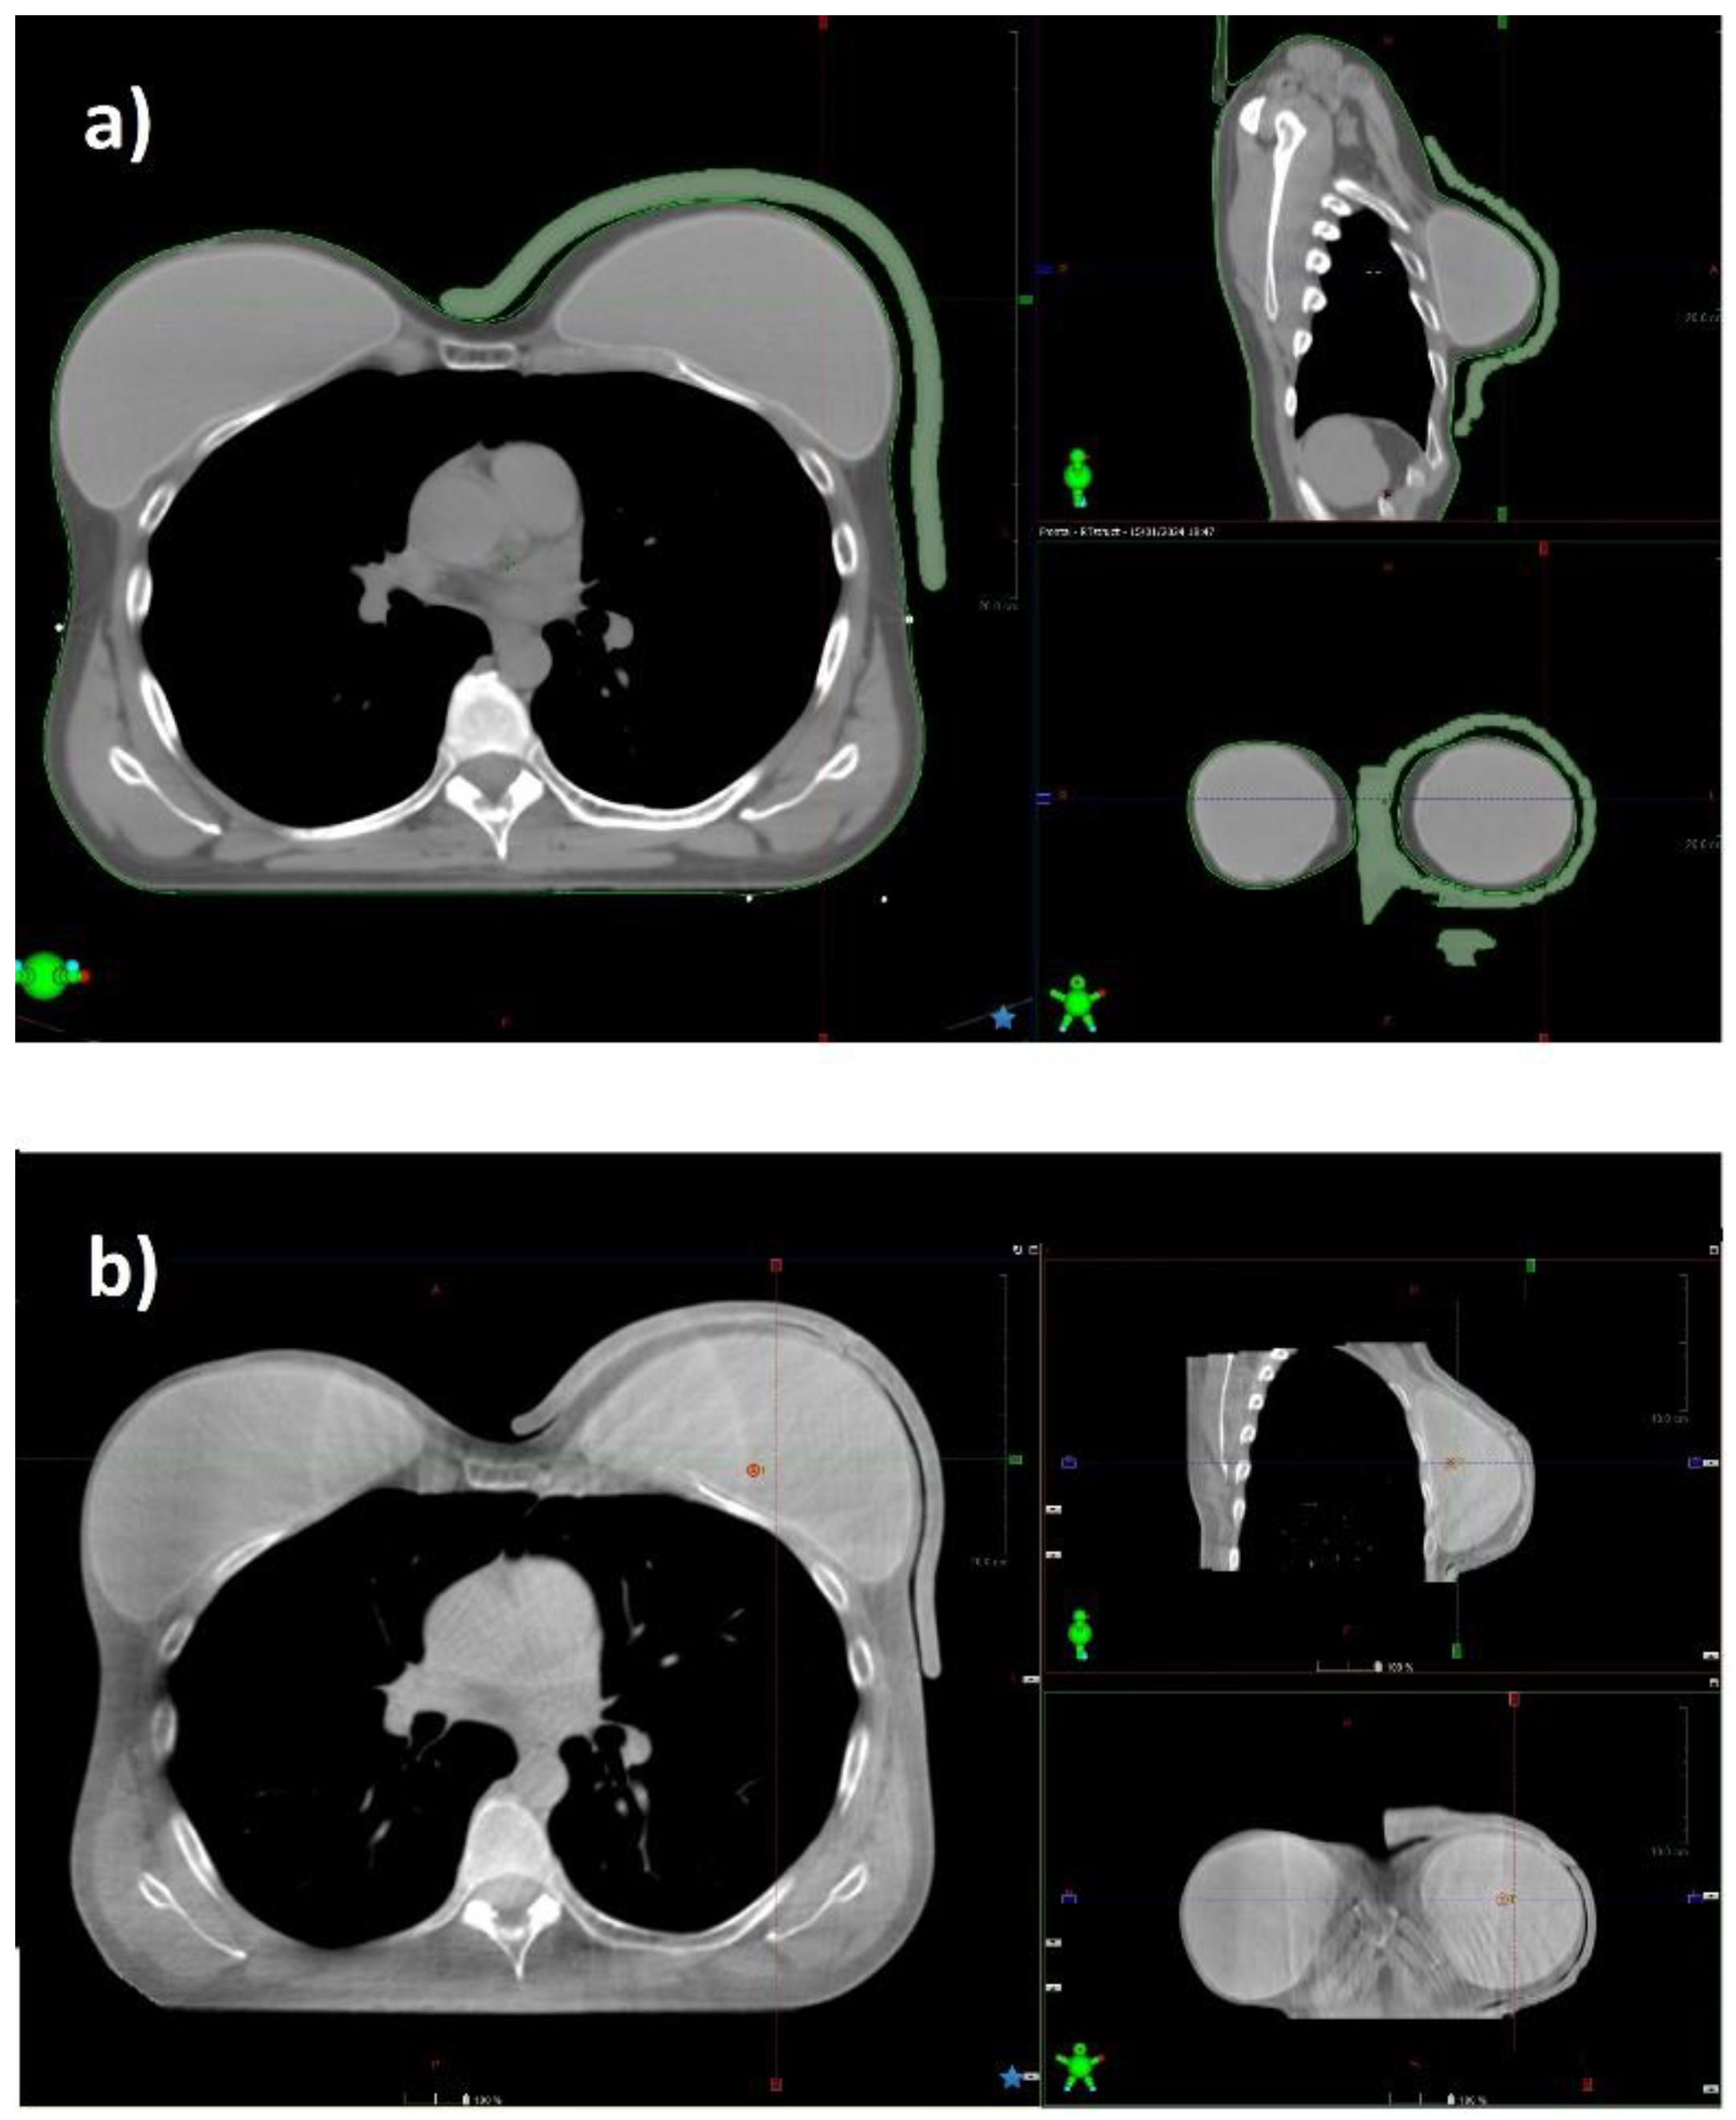

Ensuring adequate contact with the skin using a standard bolus is challenging. Air gaps between bolus and skin can lead to an inadequate or inhomogeneous radiation dose delivery to the surface of the skin. At the medial and lateral borders, where the beam axis is more perpendicular to the skin, a relative dose coverage deficit near the skin is critical (Figure 5).

Figure 5. CT scan of a patient with prosthesis and standard gel bolus (a) and CBCT acquired before radiation delivery in the same patient (b). 3D bolus fits the skin without relevant air gaps.